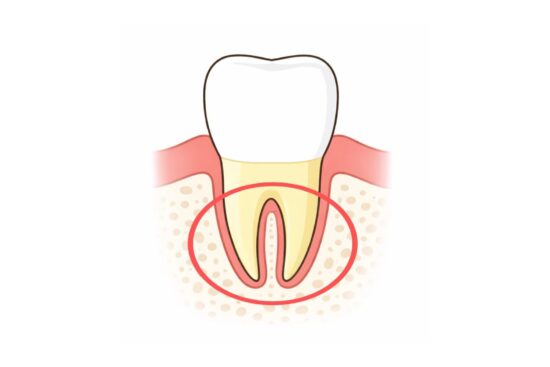

歯根って?

歯根は、歯がしっかりと骨に固定される部分です。

歯を正しい位置に動かすには、まず歯根を正しく移動させる必要があります。

歯を動かすとき、歯根だけでなく、「歯槽骨」も重要な役割を果たします。

歯槽骨は、歯根の周りにできる骨で、歯を支える大事な部分です。

歯根が正しい位置に移動しないと、この骨の位置もずれてしまいます。

さらに、歯槽骨の位置がバラバラになってしまうと、隣接している歯の歯槽骨が薄くなり、

結果的に歯周病のリスクが高まることに繋がります。